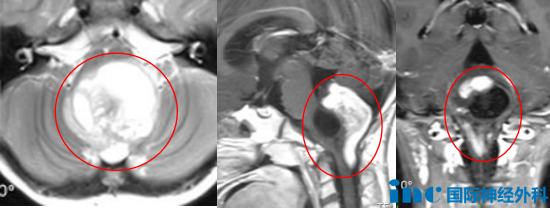

而在游泳馆的这次晕厥却加重了父母心中的不安,在急救中心进行头颅CT检查后,果真揪出了孩子数次晕厥的元凶——位于四脑室下方、枕大孔区、上段颈椎椎管偏后部,且累及脑干的肿瘤。

而满满出现的喝水呛咳、声音嘶哑等症状也正是由于该肿瘤侵袭广泛,还累及到了脑干、小脑、延髓、高位颈髓、后组脑神经及颈神经根等结构所导致的。

“在我看来,核磁共振成像显示小脑和颅颈交界处有典型的胶质瘤,累及脑干,手术是很好的选择!而且有明确的指征。对患者来说,手术时机越早越好,因为患者已经有轻微脑积水,如果不进行治疗,临床情况很快就会恶化。”

4天后,手术正式开始,巴教授与苏州大学附属儿童医院医护团队紧密配合,行经后正中入路脑干病损切除术,成功为满满安全切除肿瘤!病理结果显示为节细胞胶质瘤,Ki67指数10%。